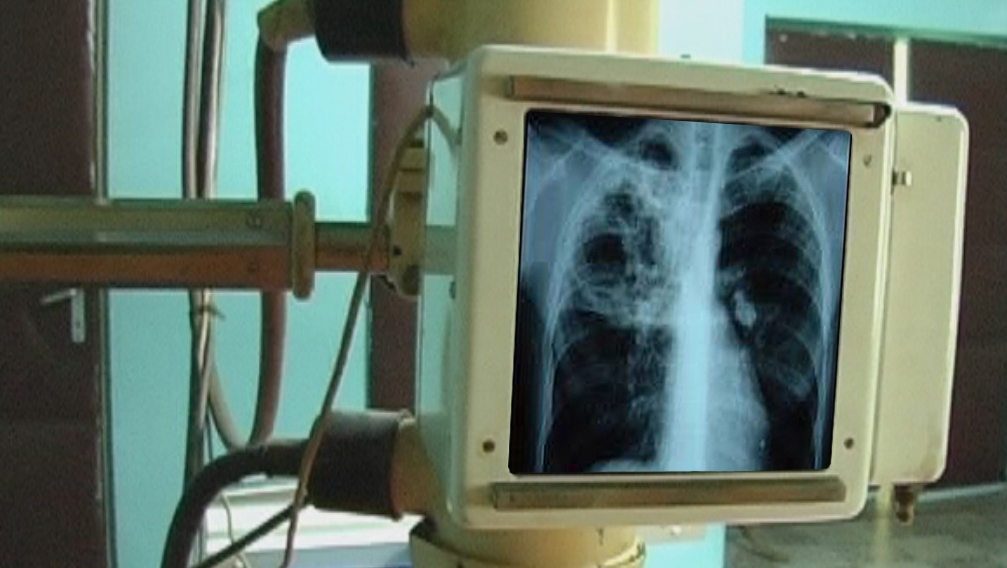

Radiografie cu tehnică de muzeu. Mai mult de jumătate din aparatele roentgen din spitalele Moldovei sunt din perioada sovietică

Mai mult de jumătate din aparatele roentgen din spitalele Moldovei datează din perioada sovietică şi sunt depăşite din toate punctele de vedere. Pe lângă faptul că nu mai sunt în stare să ofere o radiografie exactă, dozele de radiaţie emise de aceste instalaţii depăşesc limitele admisibile, spun medicii. Cea mai gravă situaţie se atestă în raioanele Călăraşi, Anenii-Noi, Briceni şi Basarabeasca.